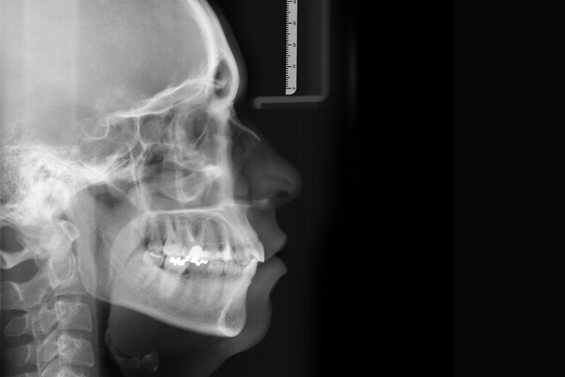

Tele Radiografias Digitais

Exame, onde se registram imagens da cabeça em posição lateral e frontal, nas quais realizam-se análises cefalométricas, que irão facilitar aos ortodontistas e cirurgiões um correto planejamento.